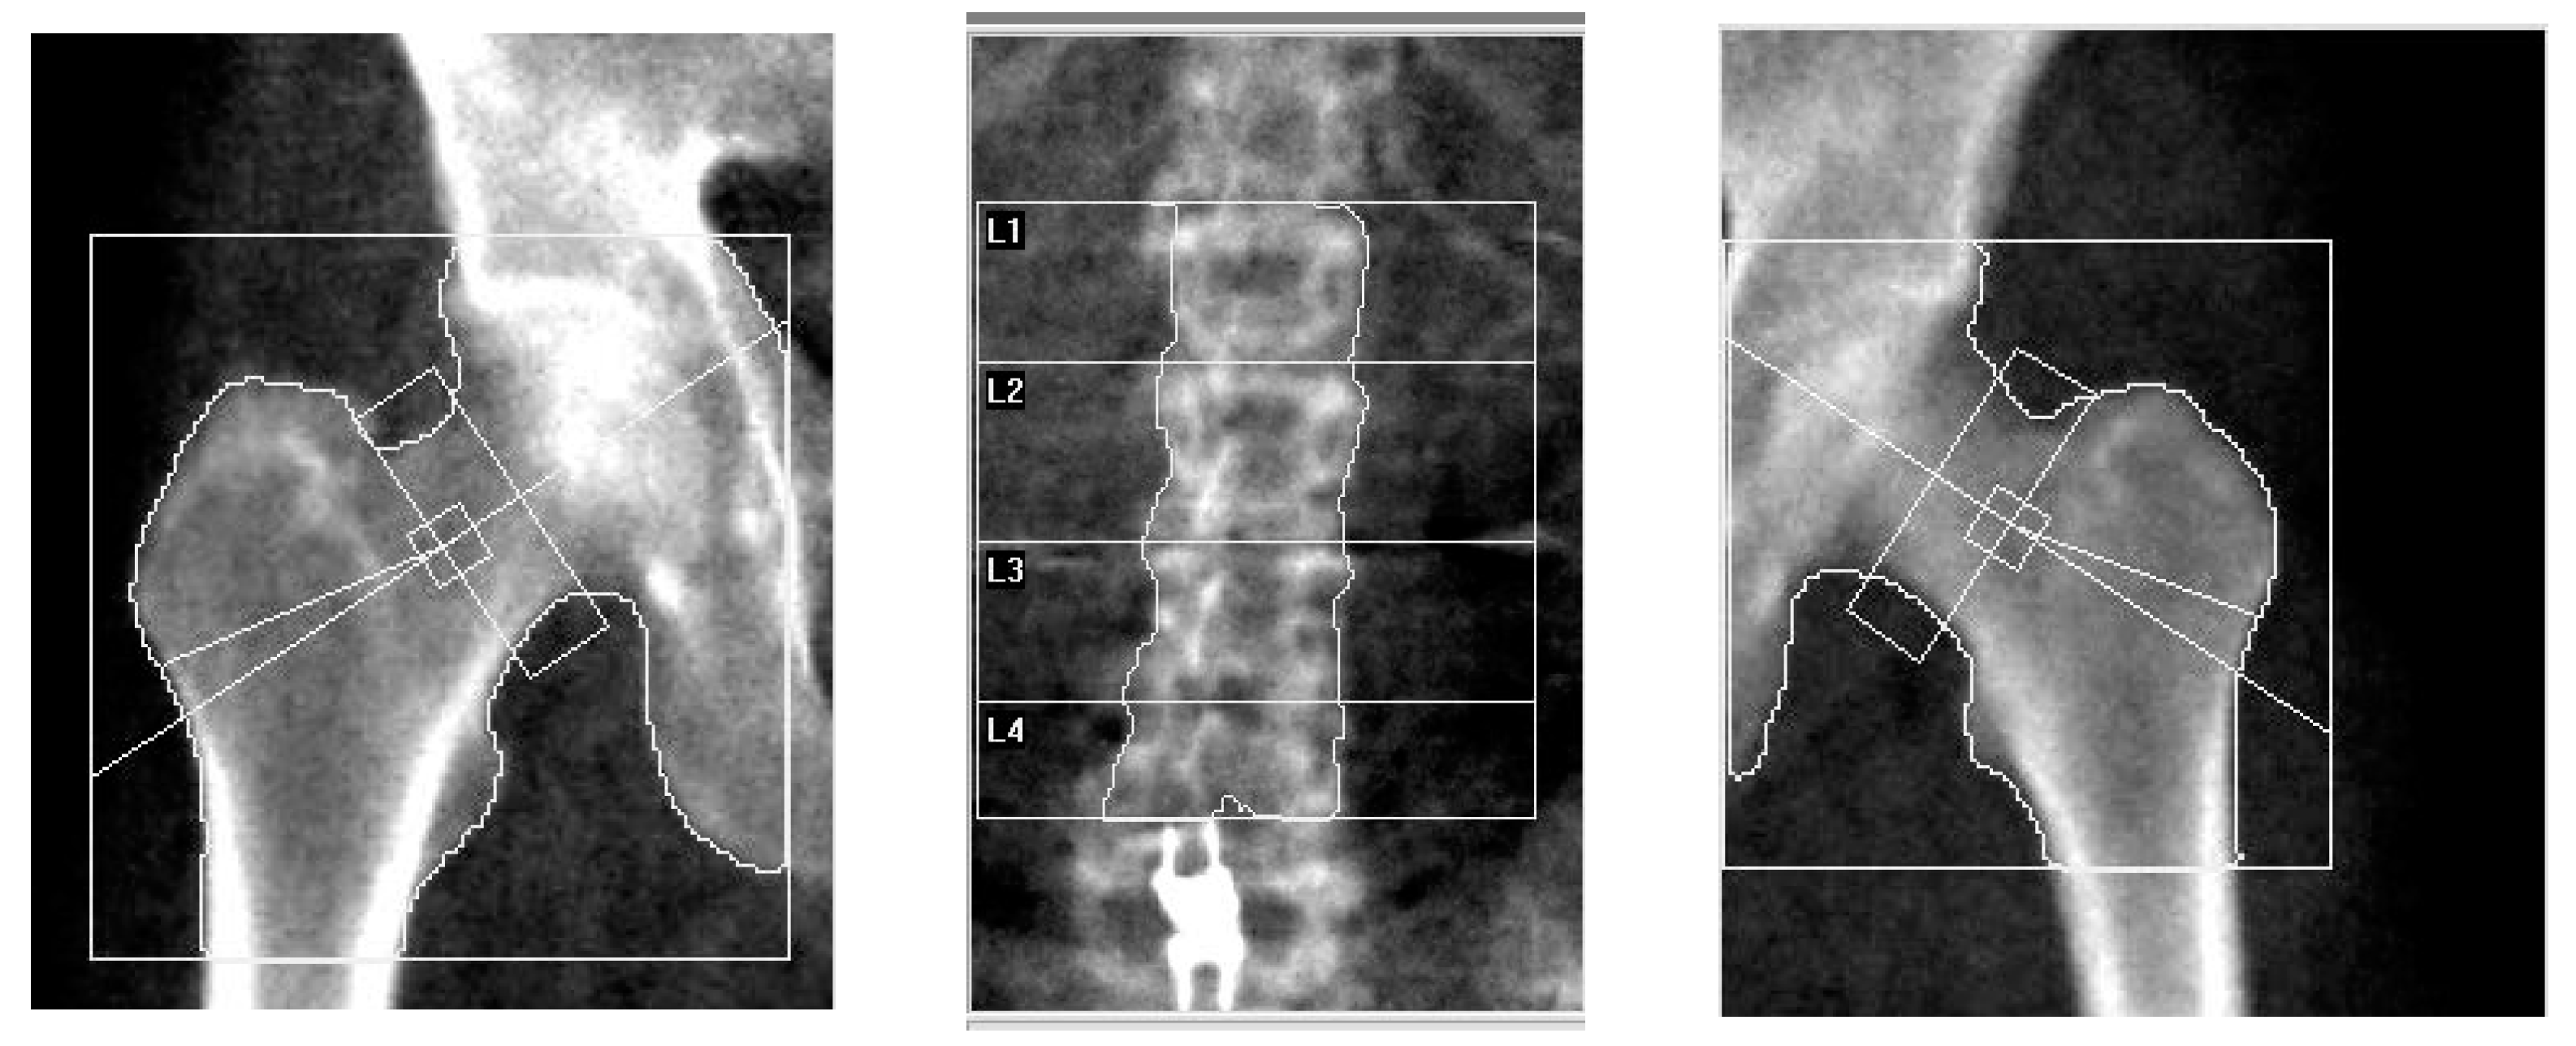

To validate the proposed methodology, it was tested on an alternative dataset that consisted of densitometry images of the pelvic joints and lower spine. All images were labeled as normal (1281 images), osteopenia (870 images), and osteoporosis (2526 images). The class distribution of the images in the alternative dataset is shown in Figure 10. The dataset was obtained at the Research Institute of Traumatology, Orthopedics, and Neurosurgery (Saratov, Russia). Examples of images from the dataset are shown in Figure 11.

Figure 11. Samples from the alternative dataset: The left pelvic joint, the lower spine and the right pelvic joint.